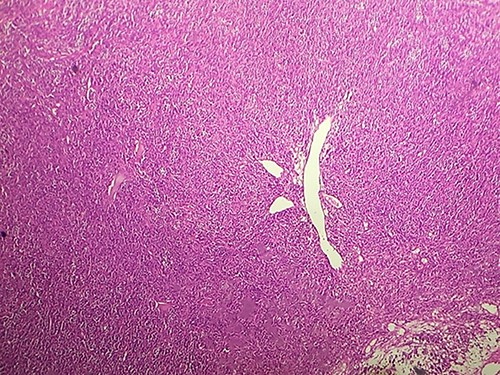

Macroscopically, the tumor was whitish, fleshy, firm, with a polylobed surface and harboring foci of necrosis. Histological examination showed densely cellular spindle cell proliferation without evidence of differentiation, with focal nuclear pleomorphism and few foci of tumor necrosis (<50%). Mitotic activity was high, estimated at 13 mitoses/10 fields at high power. (Figs 2–4) An exhaustive immunohistochemical study was necessary to classify this tumor (Cytokeratin AE1/AE3, Melan A, Epithelial Membrane Antigen (EMA), PS100, Smooth Muscle Actin (SMA), H-Caldesmone, Desmin, Myogenin, CD34, CD31, Chromogranin, Synaptophysin, CD56, P63, Beta-Catenin, STAT6 and SOX10). Tumor cells expressed SOX10 intensely and diffusely (Fig. 5), and PS100 focal (Fig. 6). The other markers were not expressed and the Ki 67 proliferation index was estimated at 60%.

HE section showing tumor cells pleomorphisme and mitotic figures (blue arrow) (x40).

Malignant tumors of the peripheral nerve sheaths are lesions that can sometimes be responsible for expansion of the nerve from which they originate. Depending on the stroma and cellularity, tumors can be fleshy, fibrous or gelatinous. Macroscopically, MPNSTs are large masses, producing swelling of major nerves. Microscopically, most MPNSTs have a richly cellular fasciculated architecture made up of generally monomorphic spindle cells with eosinophilic cytoplasm of hyperchromatic rounded or oval nuclei and indistinct cell boundaries. There is often some degree of nuclear pleomorphism. Mitotic figures are more often found in intermediate and high-grade tumors and therefore more rarely in low-grade MPNST. Some cases of MPNST show high cellularity and diffuse throughout the tumor, with a pattern of fascicular growth similar to fibrosarcoma or monophasic synovial sarcoma. Most often, however, tumors are composed of relatively hypocellular areas alternating with hypercellular areas showing perivascular emphasis, resulting in a mottled appearance at low magnification. The extracellular matrix in less cellular areas is usually myxoid, which can be abundant in up to 10% of cases. Clusters of small rounded blood vessels are commonly seen in high-grade tumors [1].